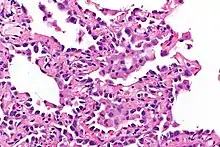

Micrograph showing multifocal micronodular pneumocyte hyperplasia. H&E stain.

Microscopy

- Well-demarcated, nodular lesions ranging 2–5 mm in pulmonary parenchyma.

- Type II pneumocytes without nuclear atypia lined thickened alveolar septa and proliferated papillary structures.

- Enlarged cuboidal cells lining mildly thickened alveolar septa.[11]

- Enlarged cuboidal cells have abundant, eosinophilic cytoplasm and large, round nuclei.[12]

- Papillary pattern with irregular margin and lymphocyte infiltration in the stroma.[13]

- No proliferation of immature smooth muscle cells suggestive of lymphangioleiomyomatosis.